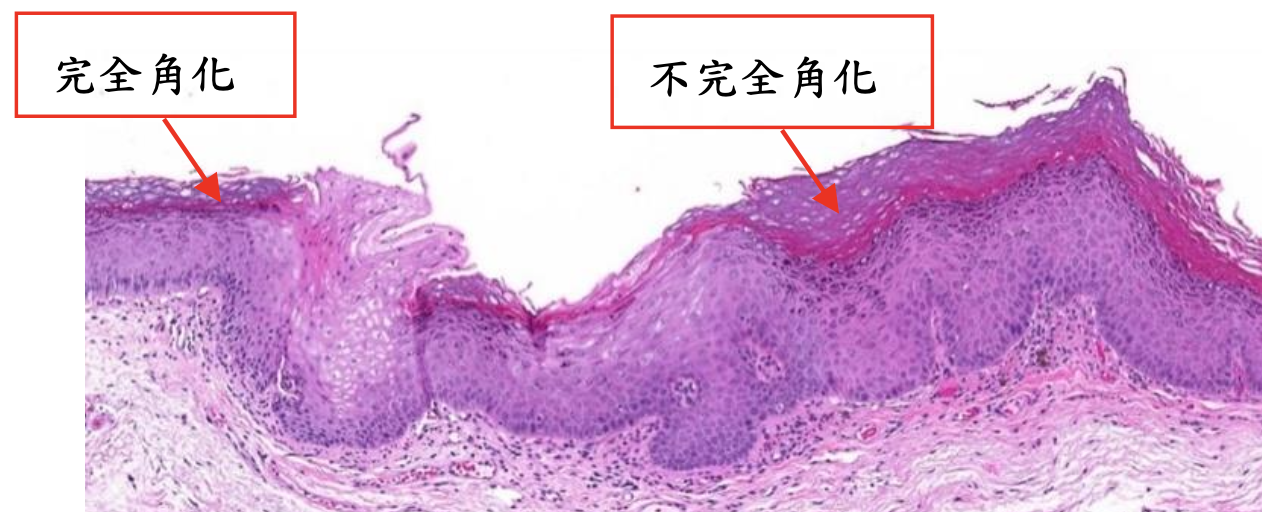

| Leukoplakia, Erythroplakia | 紅斑較嚴重,不產生角質  |

Oral epithelial dysplasia (OED)

- 分為三個程度

Mild

- 影響到下三分之一

- Basal cell 增生,變大

- Rete ridge 變寬

- 底層 keratin (紅染)

Moderate

Sever

根據和正常上皮的相似度及產生的 keratin 多寡來分級

- Grade I, well-differentiated: 產生正常量的 keratin

- Grade II, moderately-differentiated: 產生少量的 keratin

- Grade III, poorly-differentiated: 幾乎不產生 keratin